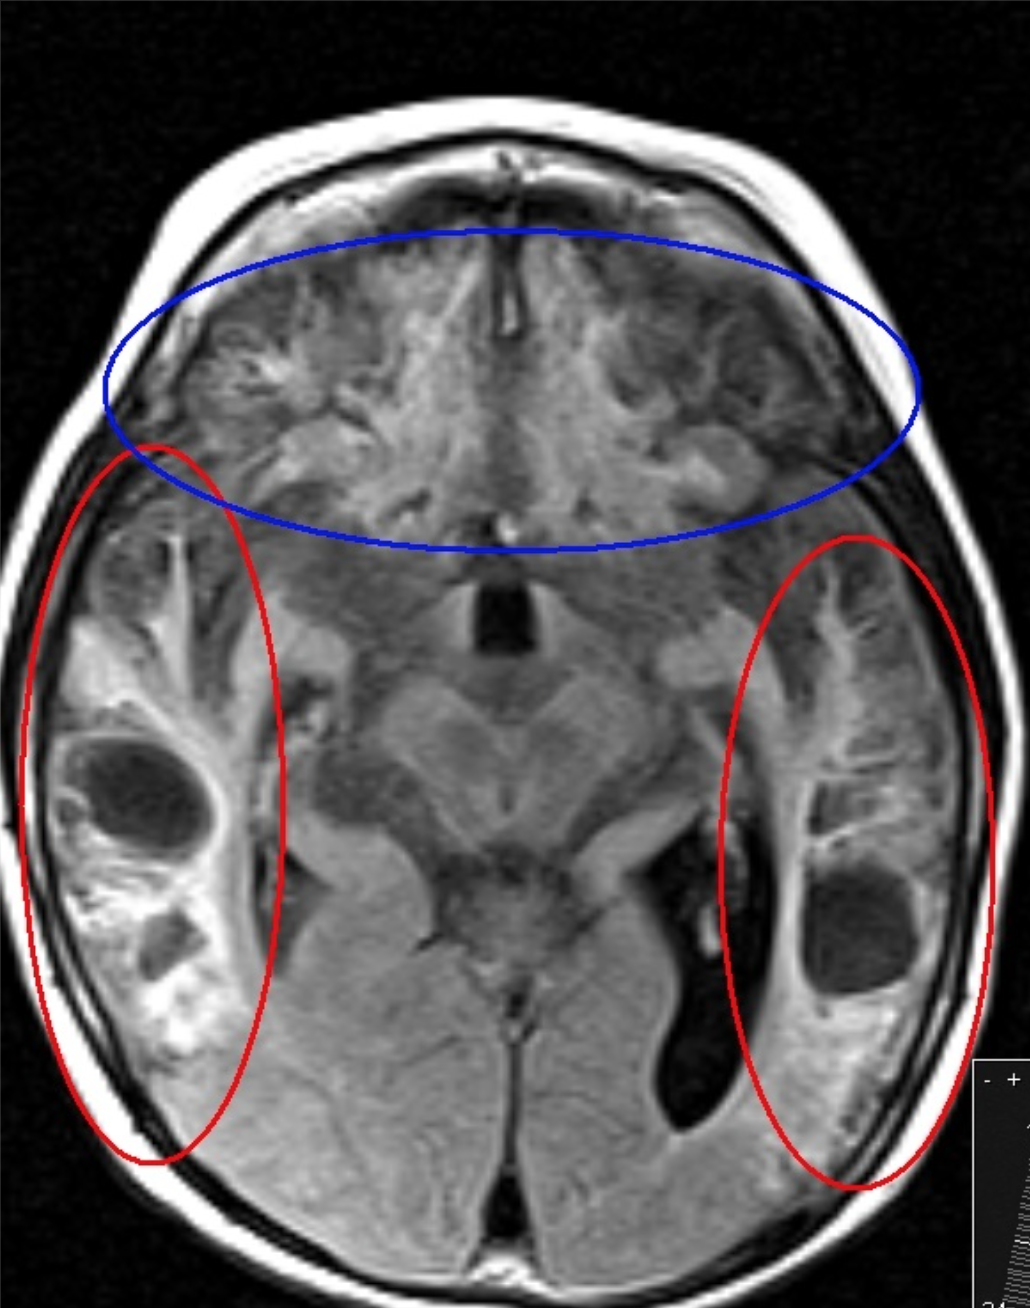

65 y/o M with rigidity.

Olivopontocerebellar atrophy